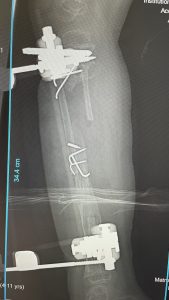

Und dies das Ergebnis nach 2-stündiger Operation.